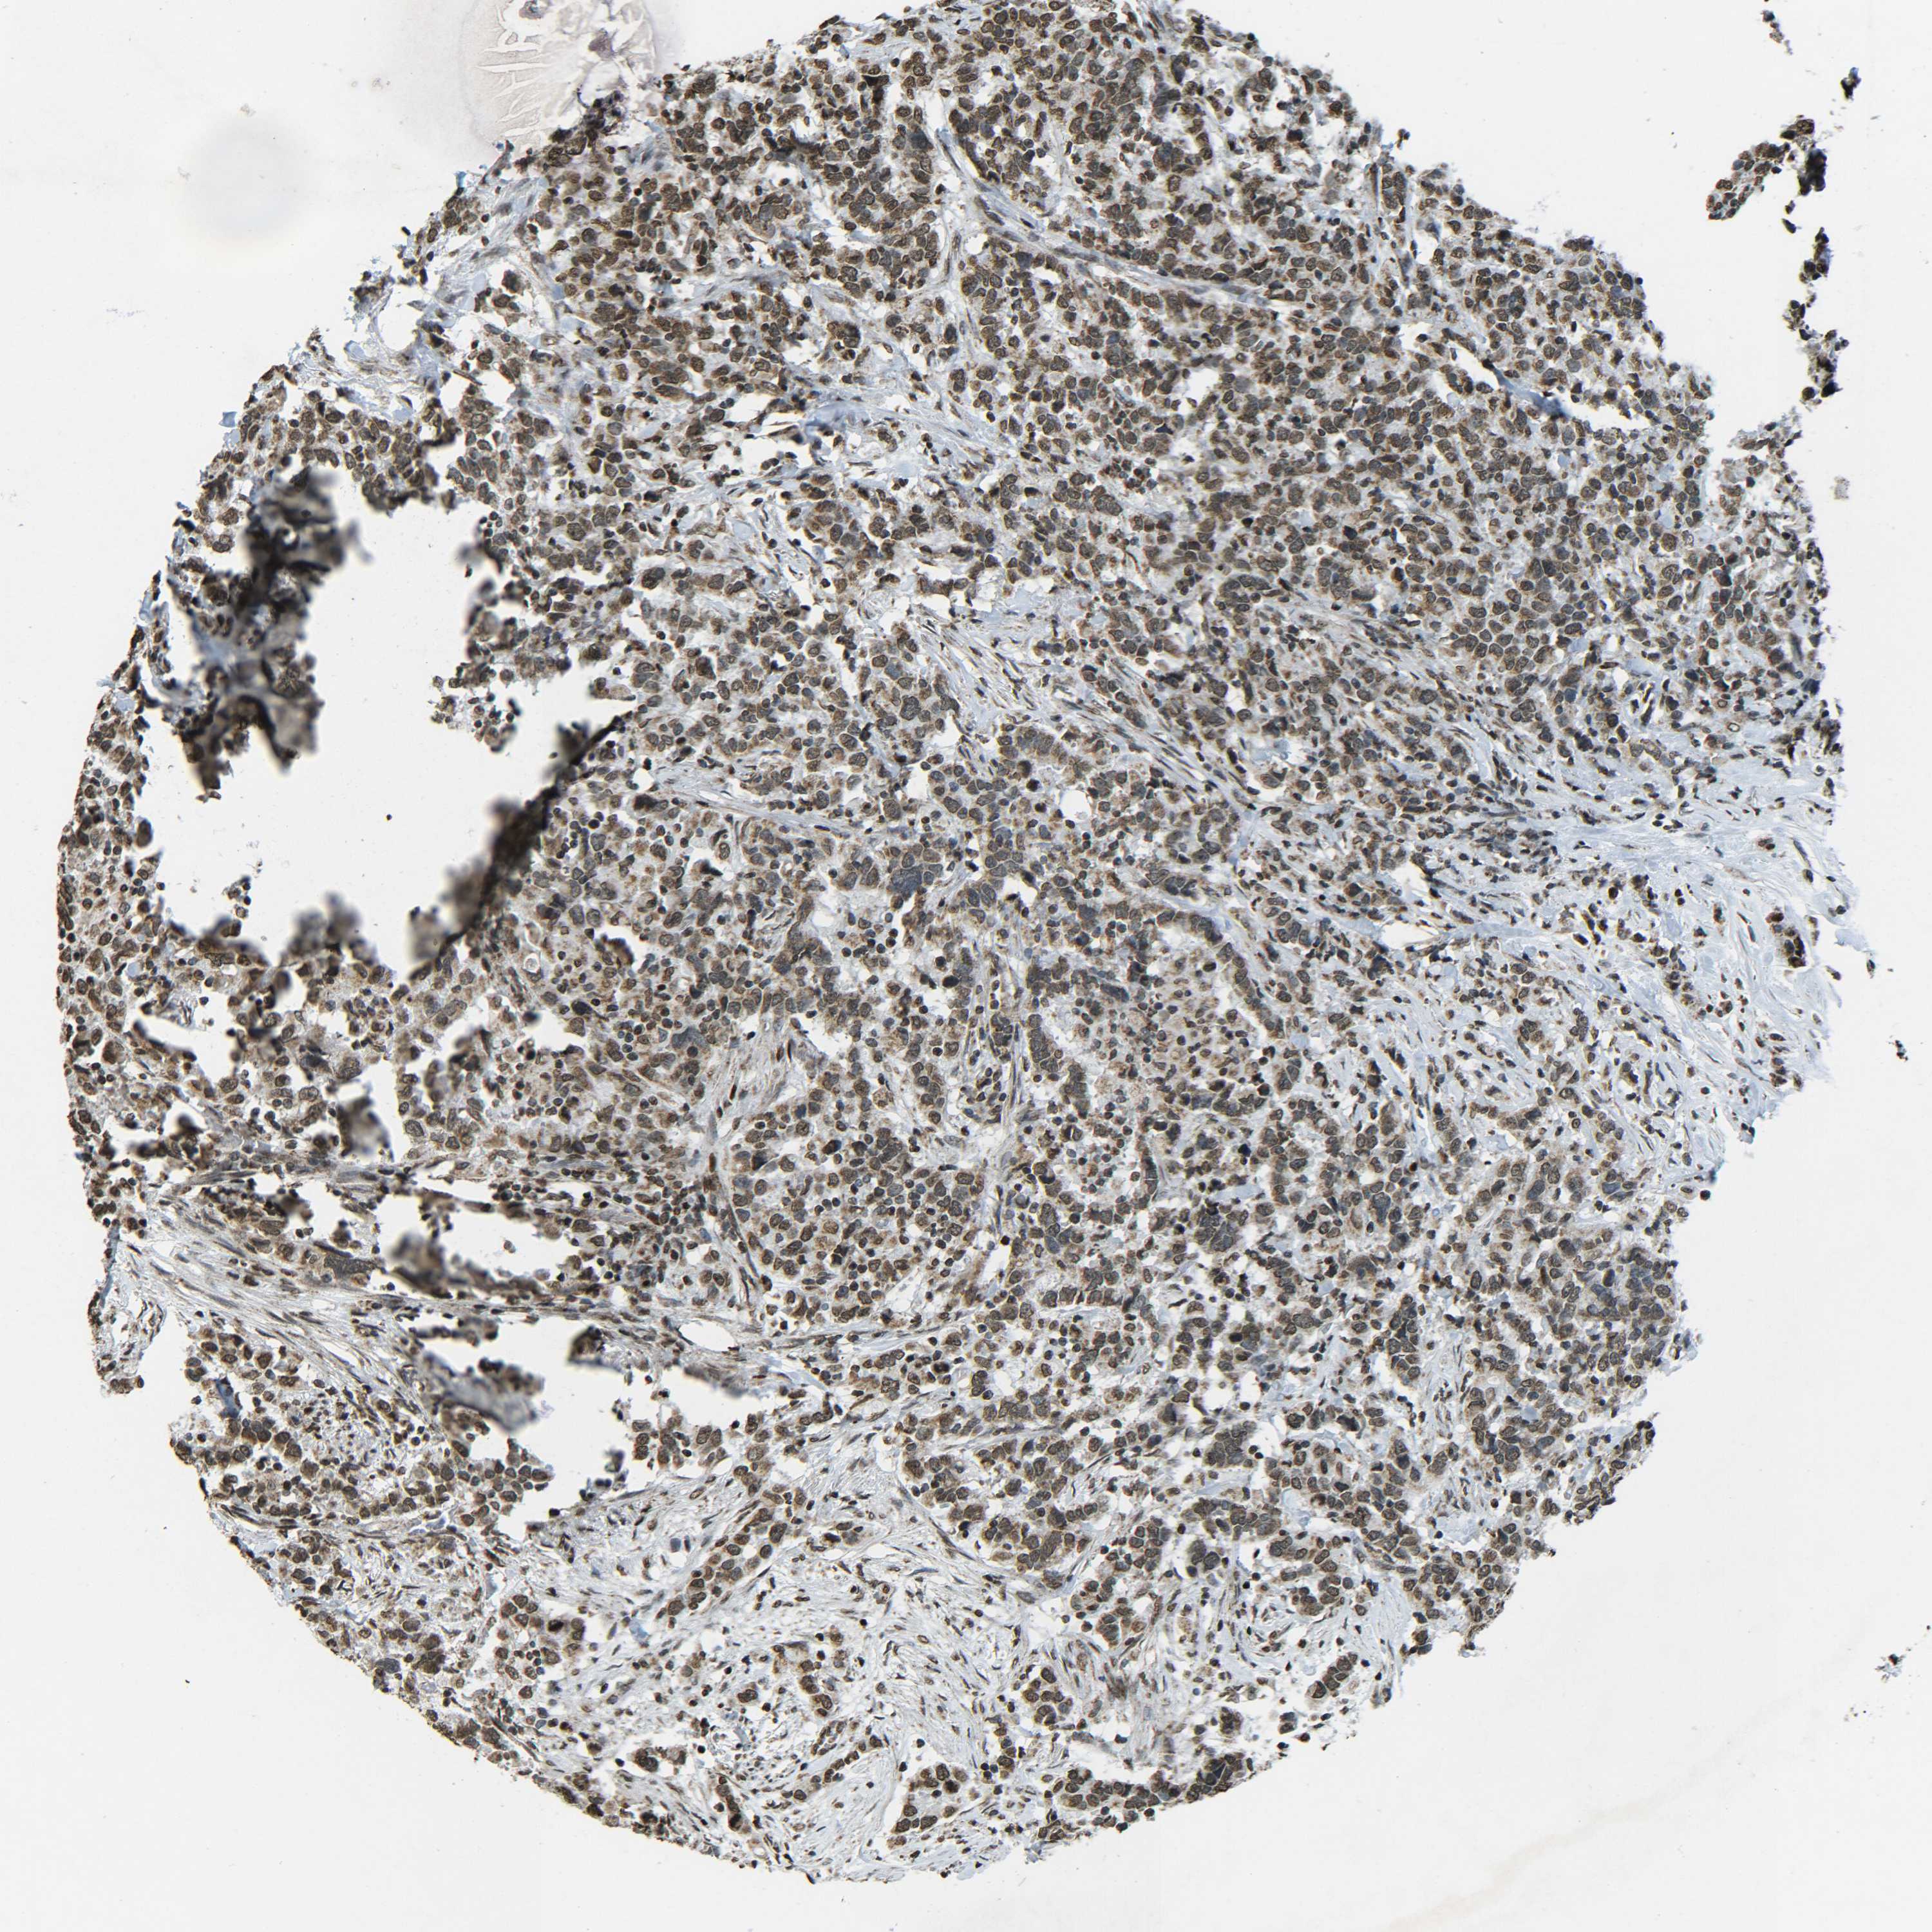

UROTHELIAL CANCER - Protein expressioni

A mouse-over function shows sample information and annotation data. Click on an image to view it in a full screen mode. Samples can be filtered based on level of antibody staining by selecting one or several of the following categories: high, medium, low and not detected. The assay and annotation is described here.

Note that samples used for immunohistochemistry by the Human Protein Atlas do not correspond to samples in the TCGA dataset.

Antibody stainingi

Antibody staining in the annotated cell types in the current human tissue is reported as not detected, low, medium, or high, based on conventional immunohistochemistry profiling in selected tissues. This score is based on the combination of the staining intensity and fraction of stained cells.

Each image is clickable and will lead to virtual microscopy that enables deeper exploration of all samples and also displays staining intensity scores, fraction scores and subcellular localization as well as patient and tissue information for each sample.

Antibody CAB012342

Staining

High

Medium

Low

Not detected

Intensity

Strong

Moderate

Weak

Negative

Quantity

>75%

75%-25%

<25%

None

Location

Nuclear

Cytoplasmic/membranous

Cytoplasmic/membranous,nuclear

Urothelial carcinoma, High grade